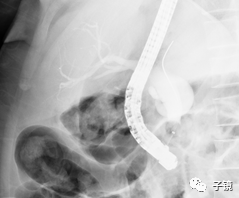

操作快两小时了,镜子固定困难,太易滑镜,留置鼻胆管,结束战斗。

取石球囊怎么取石“ERCP球囊取石细节讨论”学习笔记_https://www.jmylbn.com_新闻资讯_第12张

后记:术后患者无不适,术后第五天行鼻胆管造影,未见结石残留,造影剂排泄通畅,拔除鼻胆管后出院。